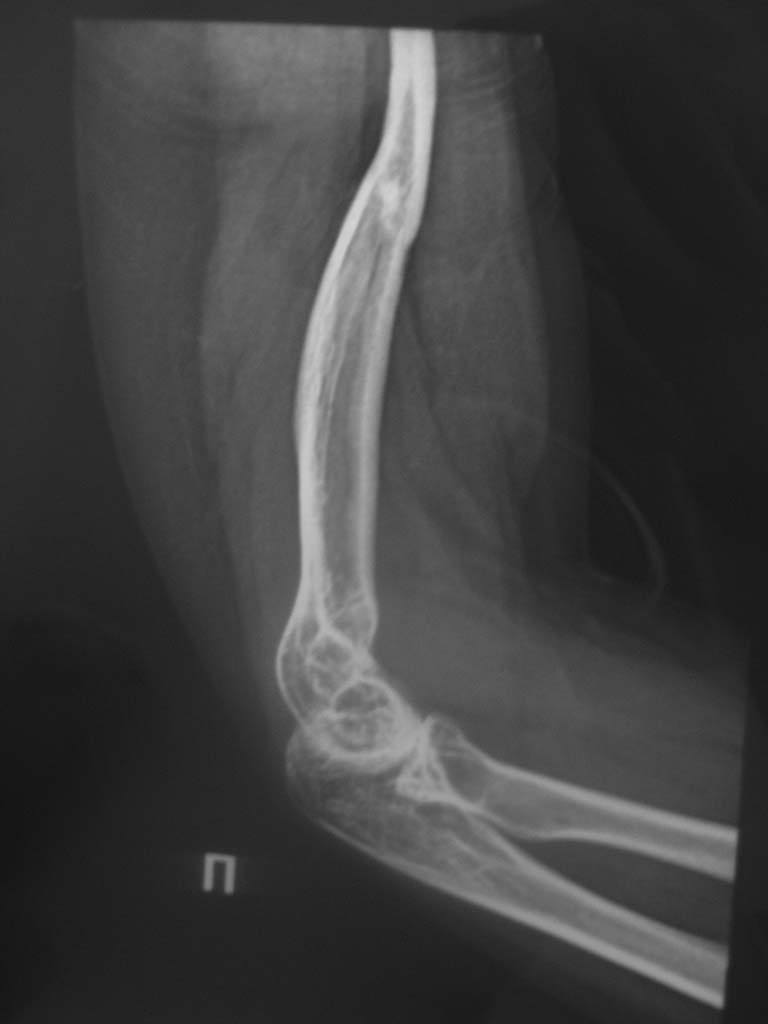

Игорь Владимирович . Пишу подробно. Больная травму получила в детстве (в

1996г) . Через год после травмы было подозрение на опухоль головки плеча

(со слов больного), оперирована - резекция опухоли, артродез правого

плечевого сустава с перемещением аутотрансплантата из малоберцовой

кости.  Послеоперационный период спокойный. Со слов больной, артродез

состоялся. Года 3 назад почувствовала боль. (ударилась). В настоящая

время движенией в плечевом сустава нет. В локтевом и лучезапястном

суставах движения не ограничены, в полном объеме.   Функция предплечья в

норме.  Выложу рентгеновские снимки локтевого сустава. Спасибо за совет.